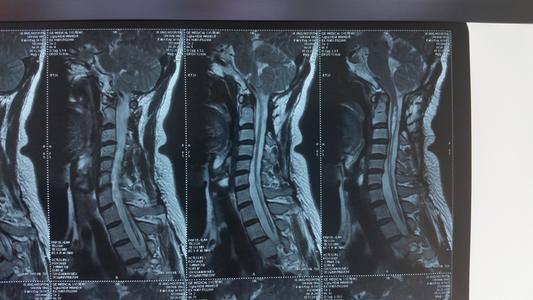

外傷性脊髓空洞(癥)通常是由于脊髓損傷、變性、軟化以后形成的脊髓萎縮,引起脊髓內(nèi)微囊裂隙或局限性中央管擴(kuò)張。

臨床表現(xiàn)為脊髓內(nèi)管狀空洞形成并腦脊液集聚擴(kuò)張,實(shí)際上是脊髓中央管積水的表現(xiàn),主要與外傷造成的腦脊液循環(huán)不暢有關(guān)。